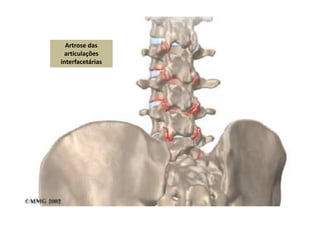

Artrose

Artrose das

articulações

interfacetárias

Síndrome Facetária (Doença Zigoapofisária)

• As facetas lombares são a segunda principal causa mais comum de dor

lombar crônica, respondendo por cerca de 40% dos casos em pacientes

idosos e 15 a 20% em pacientes jovens.

• As articulações facetárias são articulações sinoviais da coluna vertebral

que facilitam a flexão e a extensão, resistindo ao deslizamento para frente

e à torção.

Assim como outras articulações sinoviais, elas podem ser lesadas, adquirir

artrose e se tornarem dolorosas.

• Os pacientes com essa condição têm, em geral, mais de 50 anos (embora

essa condição possa ocorrer em qualquer idade) e se apresentam com dor

lombar, a qual pode irradiar-se até a nádega ou o joelho.

Raramente a dor direciona-se à perna e ao pé.

Os padrões de dor referida são de uma dor profunda e contínua e de

distribuição vaga.

A dor piora em períodos prolongados de ortostatismo, caminhadas e ao

descer degraus.

A dor melhora com os atos de sentar-se e curvar-se para a frente.